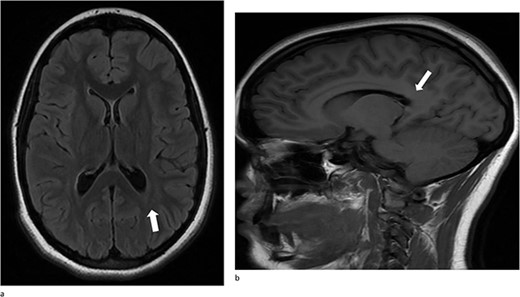

A 13-year-old female presented with an abrupt onset of a severe headache accompanied by two episodes of vomiting, left-sided jaw pain, nausea, and nasal congestion. She did not report any numbness, tingling, muscle weakness, or changes in vision. An initial non-contrast CT scan of the head revealed a left lateral intraventricular hemorrhage, (Fig. 1a). There were no intraparenchymal hemorrhages, midline shifts, or extra-axial fluid accumulations. MRI revealed a hemorrhagic lesion measuring 2.1 cm × 1.6 cm × 2.6 cm, involving the left atrium and the adjacent periventricular deep white matter (Fig. 1b). There was thickening of the choroid plexus, with no significant vasogenic edema or acute extra-axial fluid collection, and no signs of brain herniation.

(a)–(d) Demonstrates evidence of a hemorrhagic lesion involving the left atrium and adjacent periventricular deep white matter with a moderate amount of intraventricular hemorrhage within the left ventricle.

At her 12-week post-operative evaluation, follow-up MRI scans showed no residual or recurrent disease, as illustrated in Fig. 5. This patient’s genetic workup has demonstrated no propensity for neoplastic disease so far and she has resumed customary activities and routines.

(a) and (b) Stable postsurgical findings compatible with gross total resection of left atrial and adjacent periatrial tumor. No MRI evidence of residual/recurrent mass, with normal ventricular size.